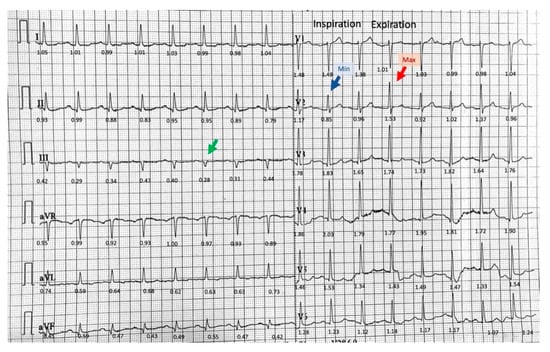

2.3. Diagnostic Assessment and Therapeutic Intervention

3.1. Phasic Variations in the QRS Complex Amplitude

3.2. Isolated Very Low Amplitude QRS Complex in Frontal Leads